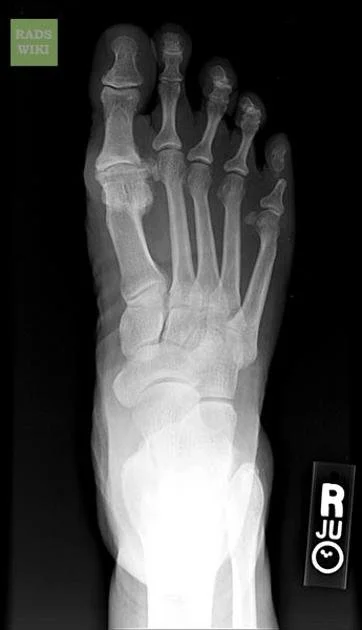

X-rays are commonly used to confirm the diagnosis and may show joint space narrowing, bone spurs, and degenerative changes of the MTP joint. Advanced imaging is rarely required but may be considered in select cases to evaluate associated cartilage damage or prior injury.